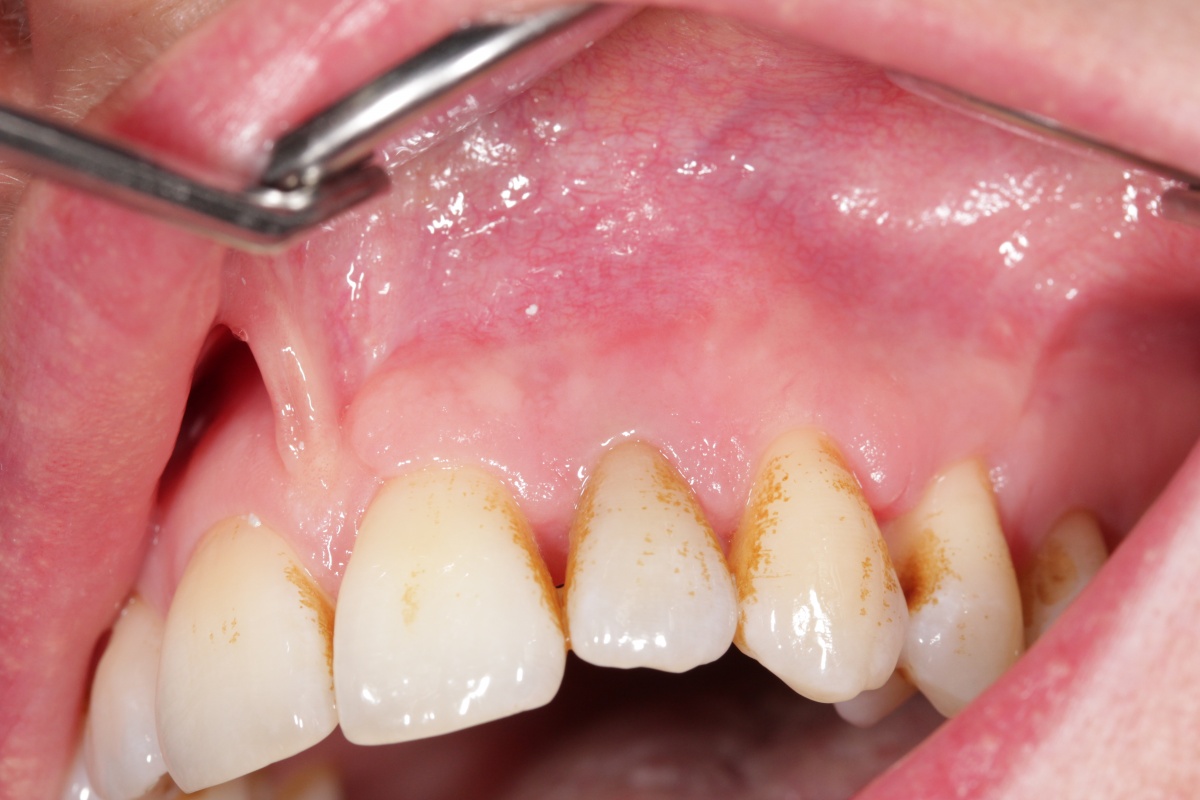

Bei der Kontrolle zwei Monate später war die Patientin vollkommen beschwerdefrei und die Fistelung ausgeheilt. Lediglich die Verfärbungen in Folge der unterstützenden chemischen Reinigung mit einem chlorhexidinhaltigen Präparat empfand die Patientin als ästhetisch störend.

die Fistelung Region 22 ist annähernd abgeklungen.

Zähne resultierten aus der Anwendung eines chlorhexidinhaltigenhaltigen

Präparates.